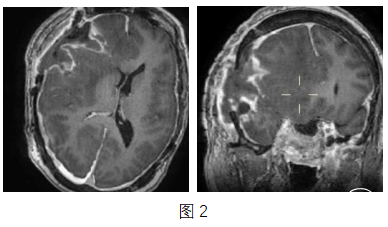

入院后给予脱水和激素治疗,考虑相关认知下降精神差系右侧额顶叶巨大占位所致,鞍区颅底占位占位效应不明显,遂先手术切除右侧额顶叶肿瘤。术后精神及认知功能有好转,术后病理考虑垂体腺癌,Ki-67(+15%)、P53(+30-40%),Ki-67≥30%、p53阳性提示预后较差,外院病理会诊支持垂体腺癌。术后复查MRI,肿瘤切除满意(图2)。病理明确后即给予替莫唑胺治疗(280mg qd,每4周用药5天,休息23天,治疗周期≥6个月),并监测血小板及白细胞数,用药三个周期后复查MRI。1年随访期内,鞍区、斜坡垂体腺瘤继续增大再次经鼻内镜手术,颅内未见肿瘤复发或出现新病灶。